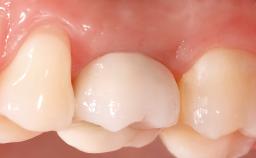

A healthy 26-year-old woman was referred for evaluation and treatment of her failing maxillary right central incisor (tooth 11). She reportedly traumatized the tooth at about age 9 and subsequently had repeated conventional and surgical endodontic procedures and fixed restorations. Despite these procedures, she had recurrent fistulas in the apical mucosa and a mid-facial pocket of 7 mm with suppuration. All other sites on the tooth probed 3 mm without inflammation. She presented with a medium biotype with triangularlyshaped teeth and a moderately high smile line, showing all of her papillas and a few millimeters of marginal gingiva in a full smile.Ceramic veneers were present on teeth 12, 21, and 22, and they were known to be somewhat bulky, eventually requiring replacement. She had a strong desire to avoid additional tooth preparation and would not consider a fixed dental prosthesis to replace tooth 11.